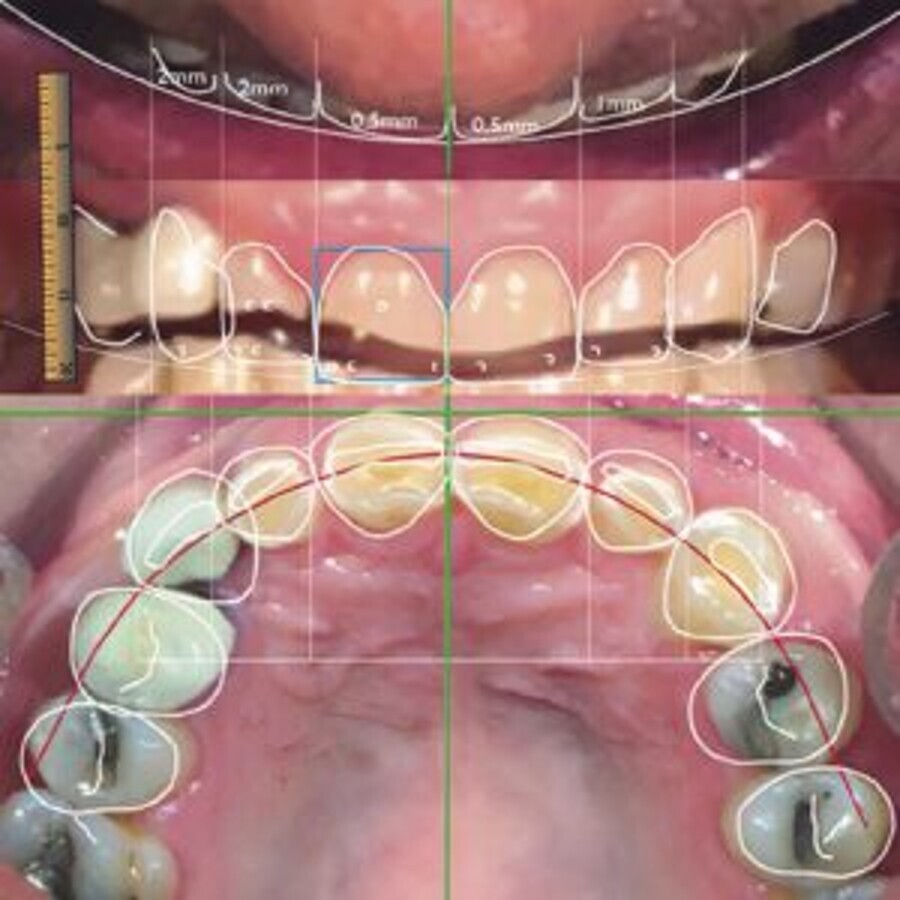

Figura 1. Las tres vistas principales de DSD calibradas unas con otras y con la regla digital (izquierda). Las líneas están superpuestas conjuntamente con los diseños, realizados a partir de fotografías de la paciente (derecha).

Esas fotografías, basadas en los análisis de video, se ajustan en la computadora a las vistas de DSD y se forma un marco de la sonrisa (smile frame) que, conjuntamente con los estudios complementarios de rutina del paciente (Rx, TAC, historia médica, examen clínico), va a guiar al equipo de trabajo en la realización del plan de tratamiento.

Se describen en detalle los 8 pasos de la configuración del marco de la sonrisa (línea media, curva de la sonrisa, proporción del ancho interdental, proporción largo/ancho de los incisivos, posición de la papila, curva del labio inferior y la curva del arco), y la importancia que tienen en la comunicación interdisciplinaria.